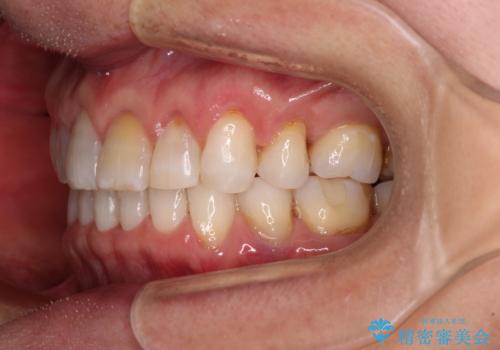

矯正治療の後戻り インビザライン・ライトでの再矯正

- 上下前歯を中心に、以前行った矯正治療の後戻りが気になるとのことで来院された患者様です。

後戻りは軽度であったため、インビザライン・ライトにて治療を行うこととしました。

矯正治療後は、再度後戻りすることを極力回避するために、下顎前歯の舌側を細いワイヤーを用いて保定することとしました。